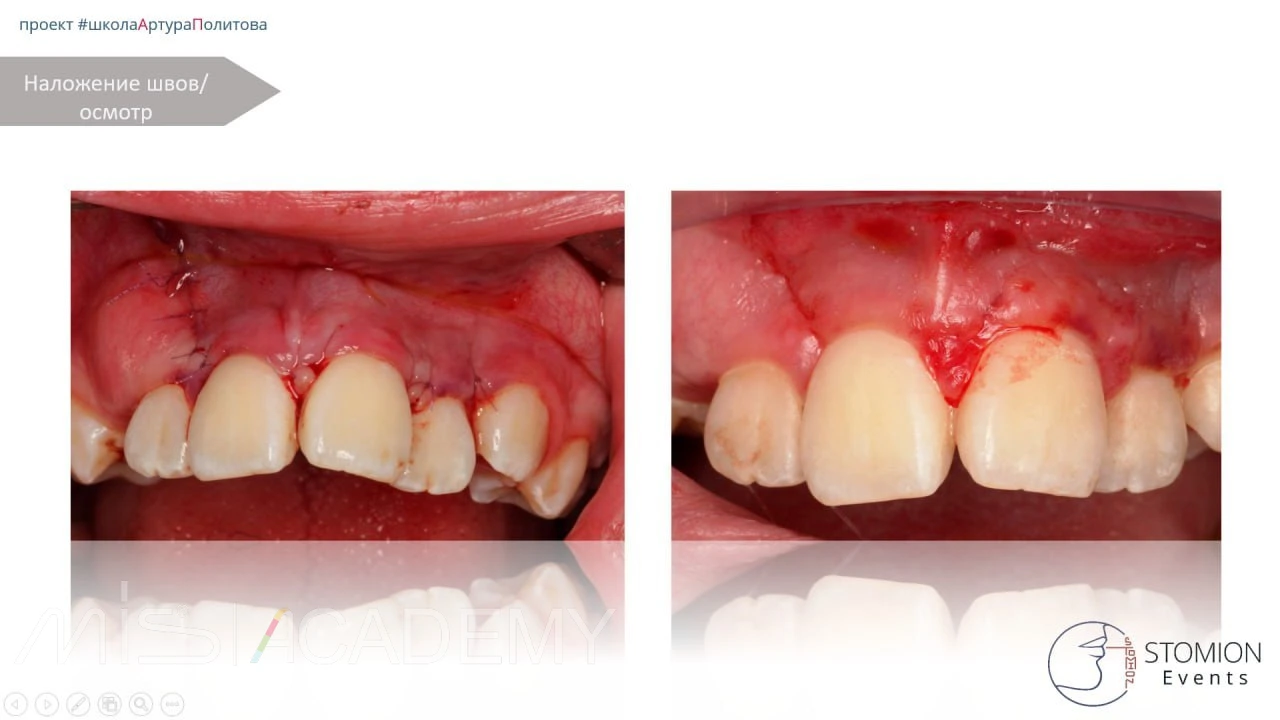

Коллапол, швы.